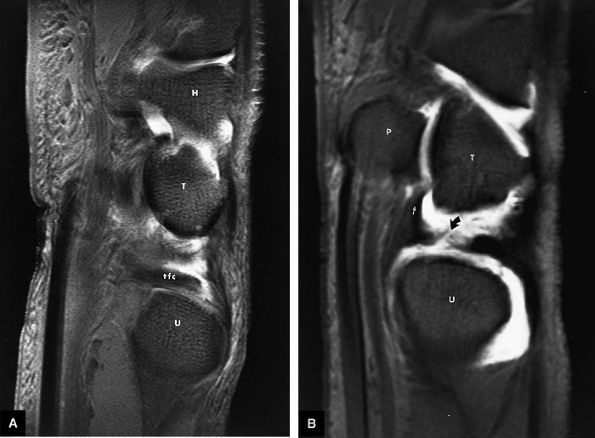

FIGURE 10.69 ● A T2*-weighted image showing the TFC complex. Black arrows, radial attachments of TFC; white arrows and UC, ulnar collateral ligament; M, meniscus homologue; pr, prestyloid recess.